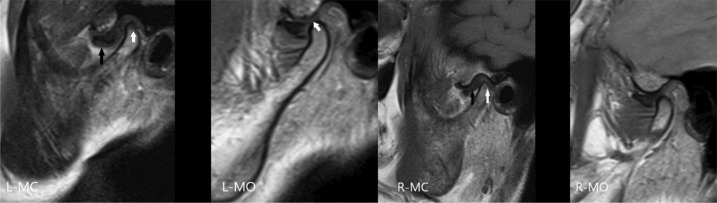

Images of Temporomandibular Joint Arthropathy in Patient with Severe Hemophilia B with Inhibitor and Patient with Type III von Willebrand Disease with Inhibitor

一名严重血友病 B 型患者(含抑制剂)和一名 III 型 Von Willebrand 患者(含抑制剂)的颞下颌关节关节病图像。